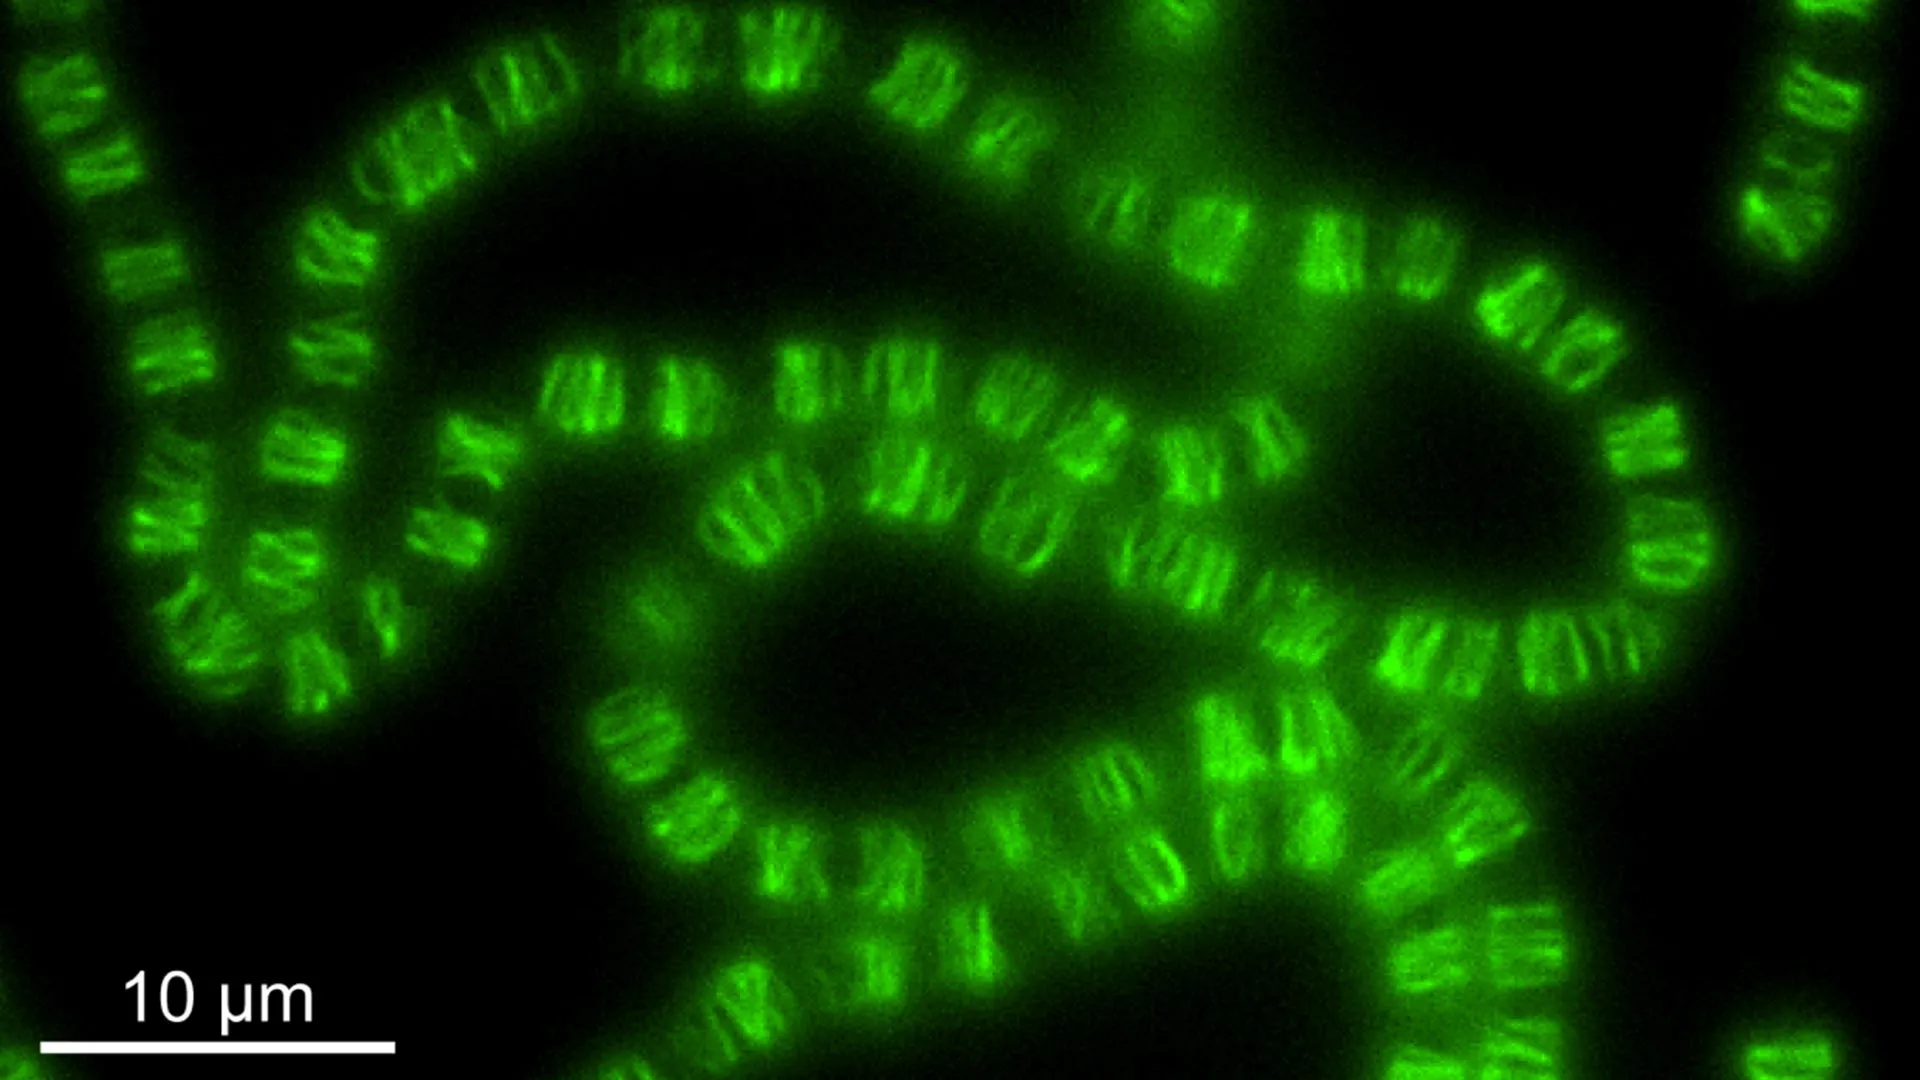

Um novo estudo publicado em 24 de março na Radiology, o jornal da Sociedade Radiológica da América do Norte (RSNA), …